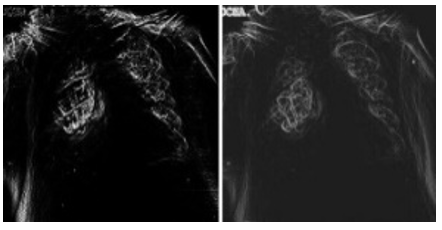

Third: the performance of the hardware system is evaluated to perform the ground truth edge detection technique, which is a method to accurately determine the boundary edges in an image by measuring the local and global structural similarity between any two images, as illustrated in Table 4 and Table 5 as well as Figure 9. In this technique, (1) represents perfect similarity, (0) represents no similarity, while (-1) represents complete dissimilarity.

Table 4 and Table 5 demonstrate the similarity between the two methods for both types of images and Peak Signal-to-Noise Ratio (PSNR) as well as Quality Factor. They illustrate the similarity of the methods for healthy images (0.8711-0.9885) is higher than that for infected images (0.8010-0.9825). As previously explained, the reason lies in the nature of the COVID-19, which increases the complexity of the edges and makes them less clear.

Figure 9. Normal and infected ground truth edge detection similarity results